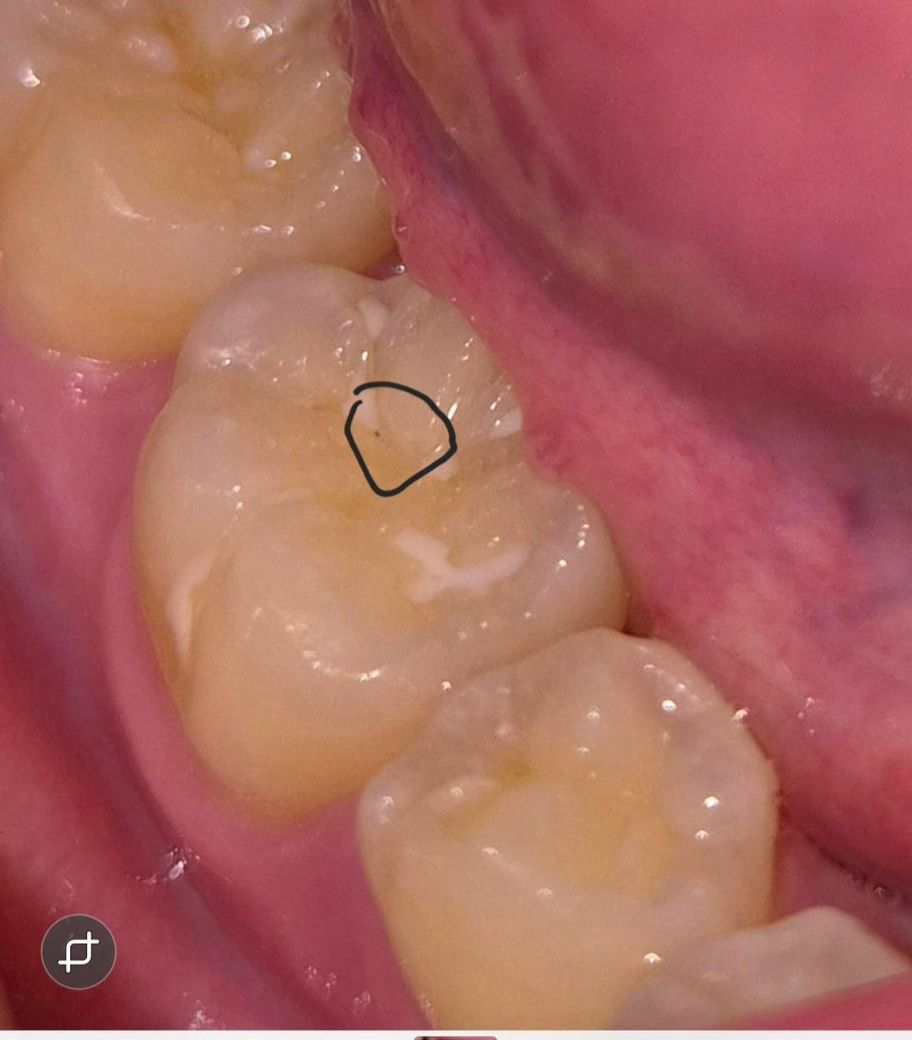

저동그라미친 부위입니다

불과한달전까지만해도 치과검진시 저런게없었는데,

갑자기 보니 까맣게 콕 보이던데

그사이 실란트가일부탈락되며 보이게된것같아요

아마도 실란트하방쪽으로 충치가 있는게아닌가싶어요. 주변이 검게보이거나 이렇지는 않던데~~ 저정도면 상태가어떤건가요

치과가긴할건데 실란트뜯어내고 충치치료할단계인거죠?

아니면 혹시 그냥 두고지켜봐도되는걸까요?

실란트가 일부 탈락하고 하방으로 약간 충치가 있어보이네요 저정도면 실란트 다 뜯고 레진 새로 해주는게 좋겠습니다